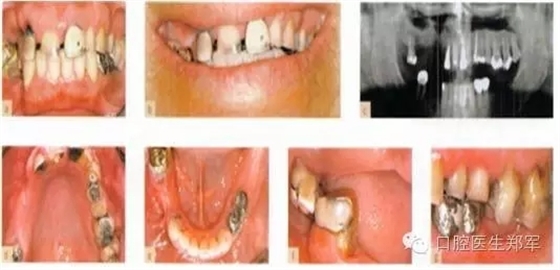

圖片5到12案例介紹了部分牙列缺損導(dǎo)致的功能缺失和美學(xué)受損。

形態(tài)缺陷的診斷包括:牙列缺損、后牙支撐減少、輕度到中度的垂直距離喪失,美學(xué)和功能障礙,以及不良修復(fù)體。

口腔疾病和功能障礙包括:繼發(fā)齲、可復(fù)性關(guān)節(jié)盤移位、繼發(fā)創(chuàng)傷、臨床附著喪失≥5mm超過30%的位點的嚴重慢性牙周炎。

圖5 a-g 局部缺牙、美學(xué)缺陷、牙列缺損、后牙牙合支撐喪失、部分牙段過度萌出、咬合垂直距離中度喪失(圖片由Dr. 0 Ghelfan提供) |